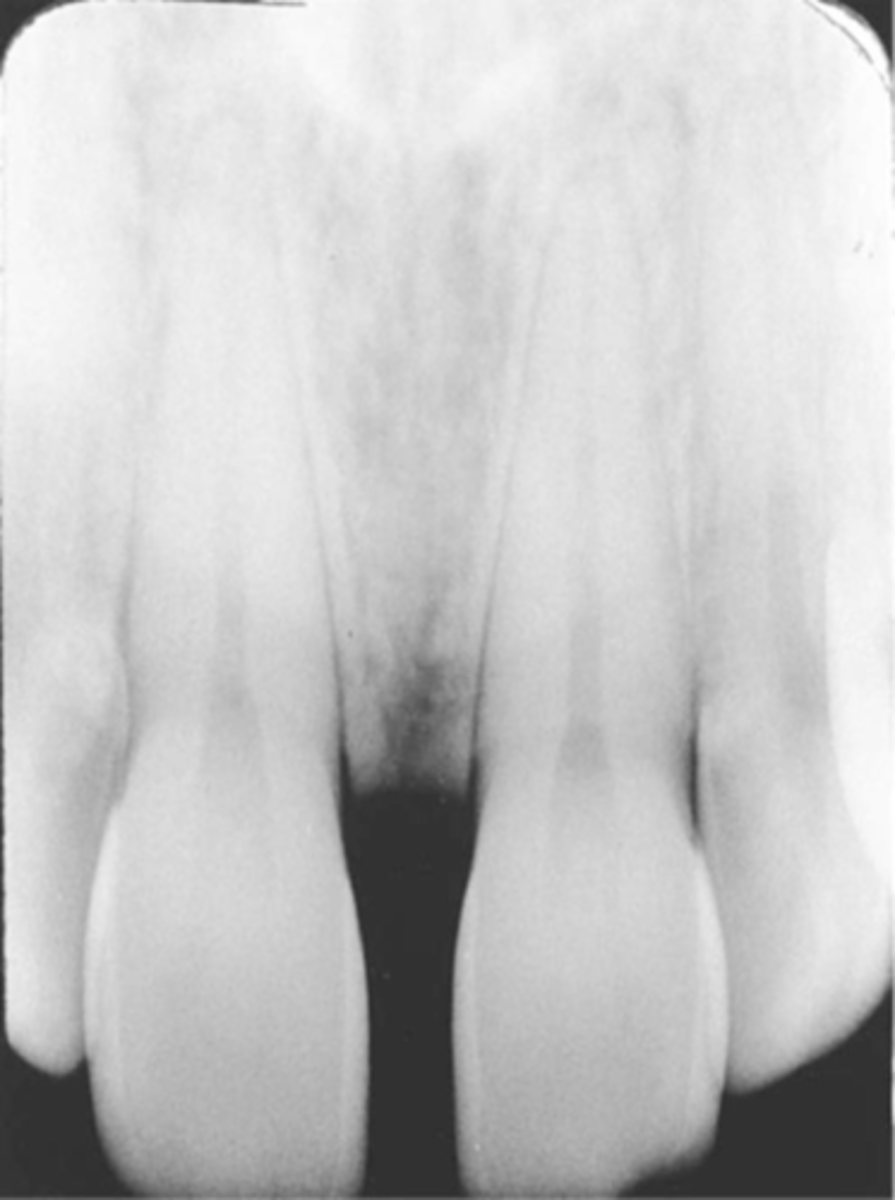

Incorrect Vertical Angulation-->Elongated Images

-Teeth appear long and distorted

-Vertical angulation was insufficient or too flat, resulting in images that are longer then the actual teeth.

-Occurs more often with the bisecting technique

-To prevent use adequate vertical angulation

Tube Head & PID-->Elongation of the Image

-Bisecting technique error

-Insufficient Angulation (not steep enough), causing elongation or increased anatomy of the teeth and cutting off apex.

3. Elongation of the image: Insufficient vertical angulation